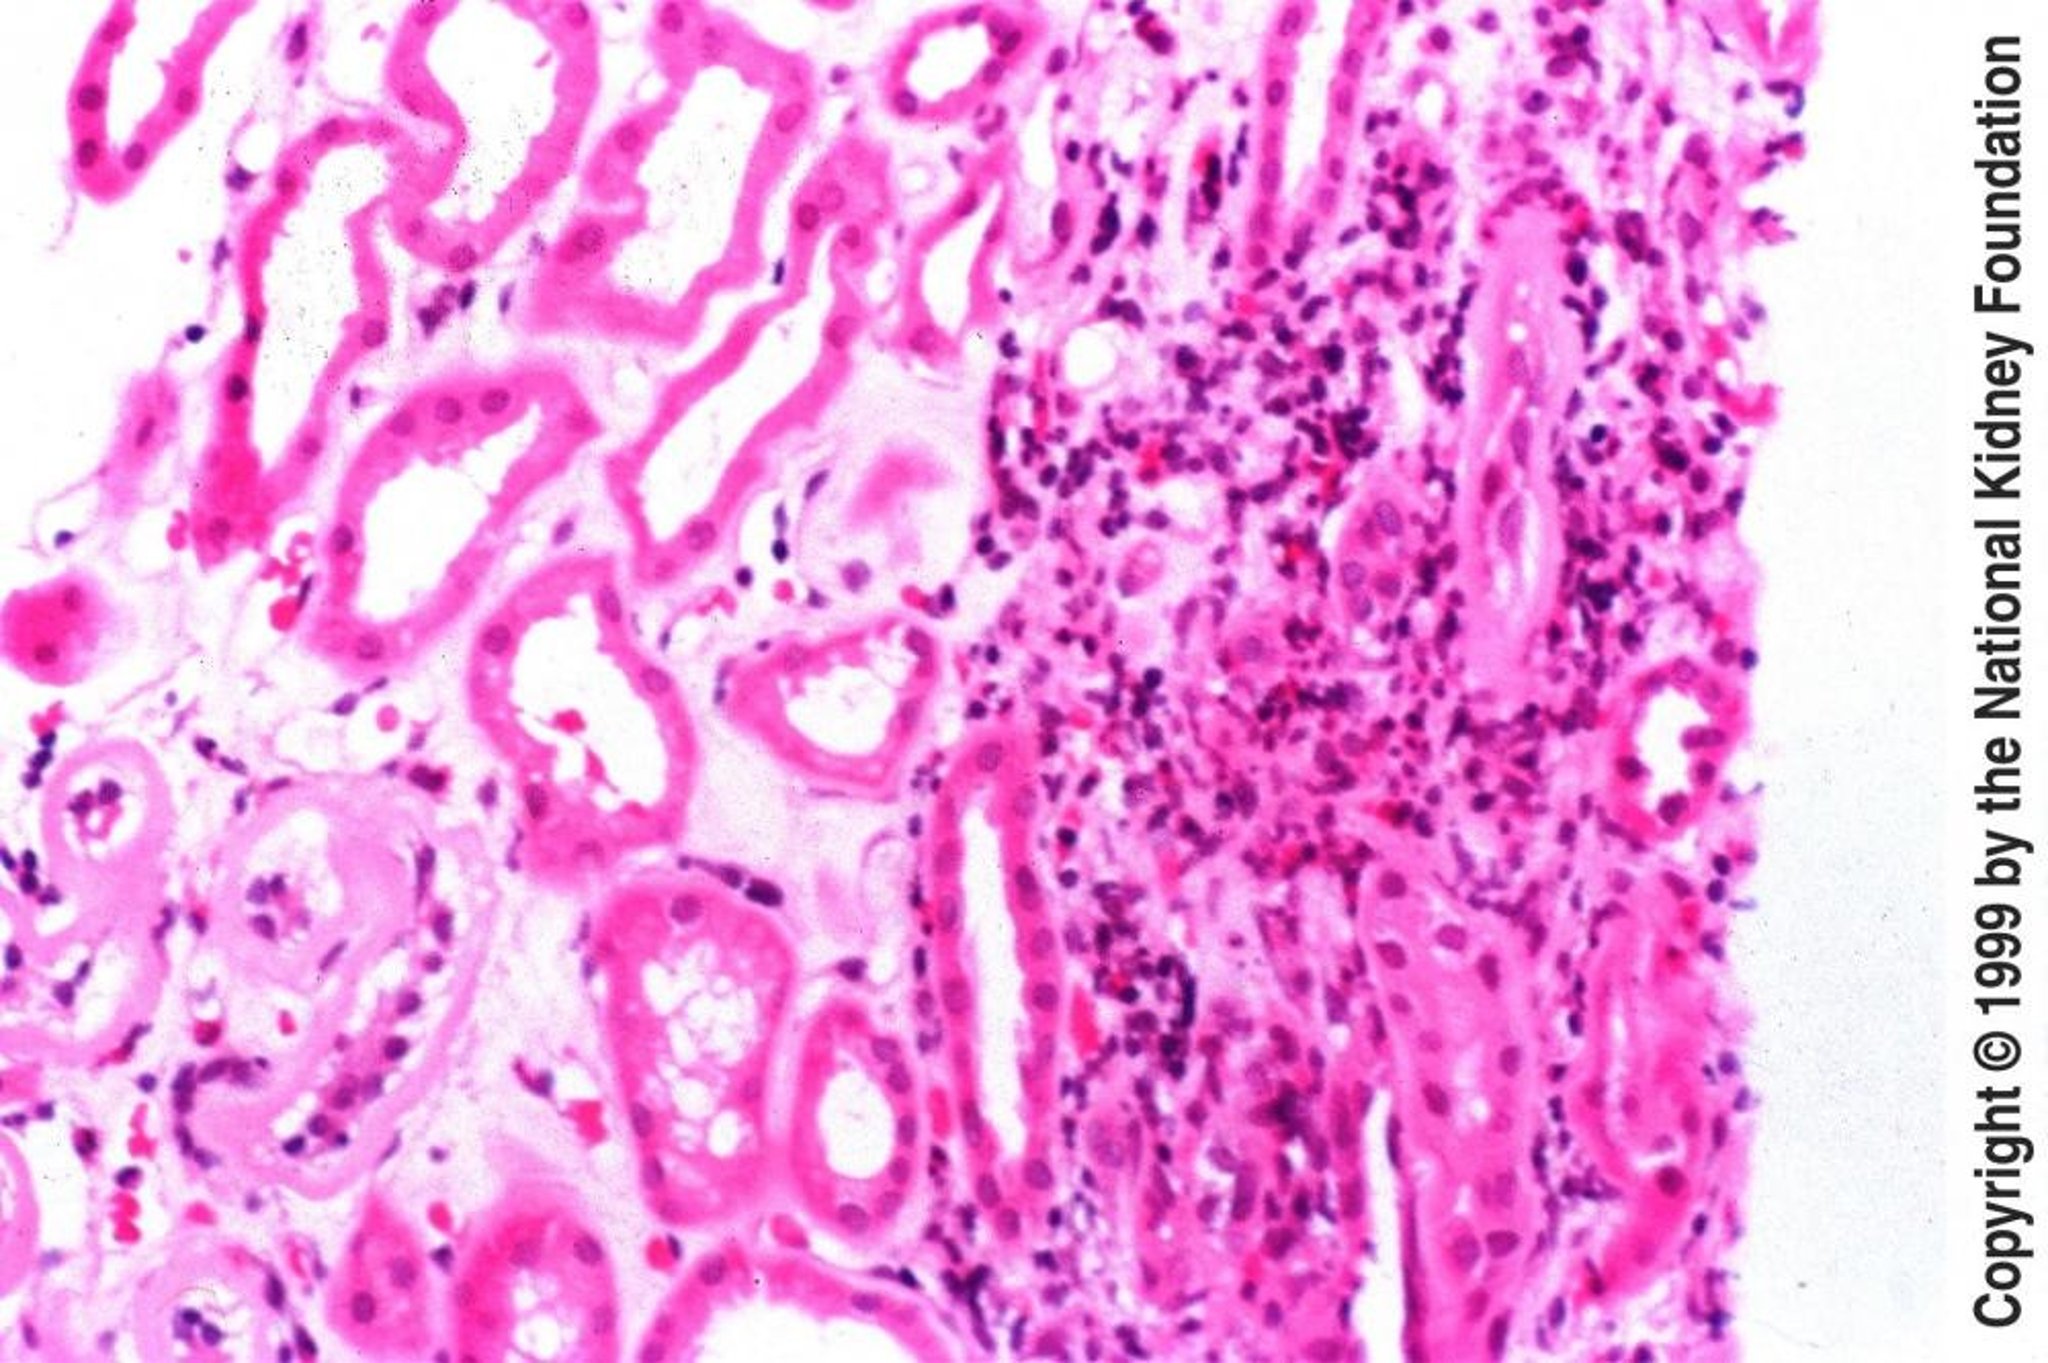

Acute Tubulointerstitial Nephritis

Biopsy specimen in acute tubulointerstitial nephritis demonstrates interstitial edema with infiltration by eosinophils, lymphocytes, and plasma cells (hematoxylin-eosin stain, ×200).

Image provided by Agnes Fogo, MD, and the American Journal of Kidney Diseases' Atlas of Renal Pathology (see www.ajkd.org).